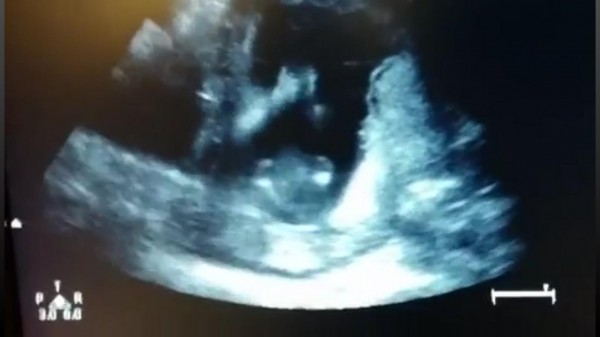

جنين يصفق داخل رحم أمه

خفق قلب والدين وطارا من الفرحة عندما رأيا جنينهما وكأنه يصفق بكفيه داخل رحم الأم، بينما يستمع إلى أغنية رددها الوالدان داخل غرفة الفحص. وبدا الجنين البالغ من العمر 14 أسبوعاً، يقلب كفيه ثلاث مرات على أغنية “Happy”، وكأنه ينفذ ما تقوله الأغنية أو ما يتمناه منه والداه، بحسب موقع “مترو” البريطاني.